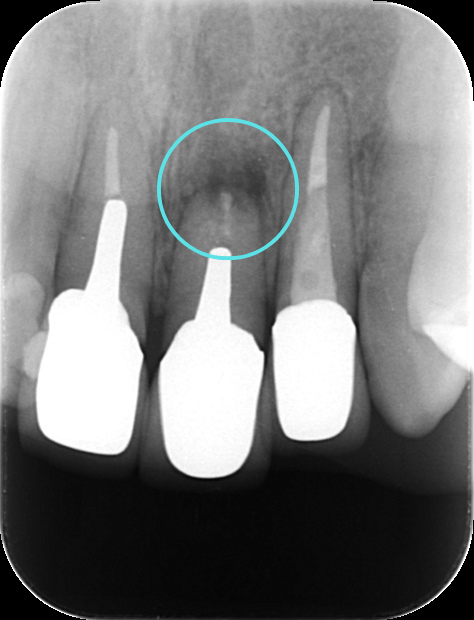

術後すぐ

術後3ヶ月のレントゲン写真

術後1年のレントゲン写真

根尖病変によって骨が溶かされてしまった空間も、歯根端切除術によって感染源が適切に除去され、根管が緊密に封鎖されると、体本来の治癒力によって再び新しい骨(新生骨)が作られていきます。 レントゲンでは、術直後は黒い影(骨がない状態)だった部分が、時間の経過とともに徐々に白く(骨が再生してきた状態)映るようになります。この「新生骨の出現」が、外科的歯内療法の成功を示す客観的な証拠となります。

今回の患者さんも、術後の定期検診にお越しいただきました。 術後6ヶ月の時点でのレントゲン写真では、手術前に黒い影として見えていた根尖病変部、および歯根を切除したスペースに、白く不透明な影、すなわち「新生骨」が順調に再生してきていることが明確に確認されました。